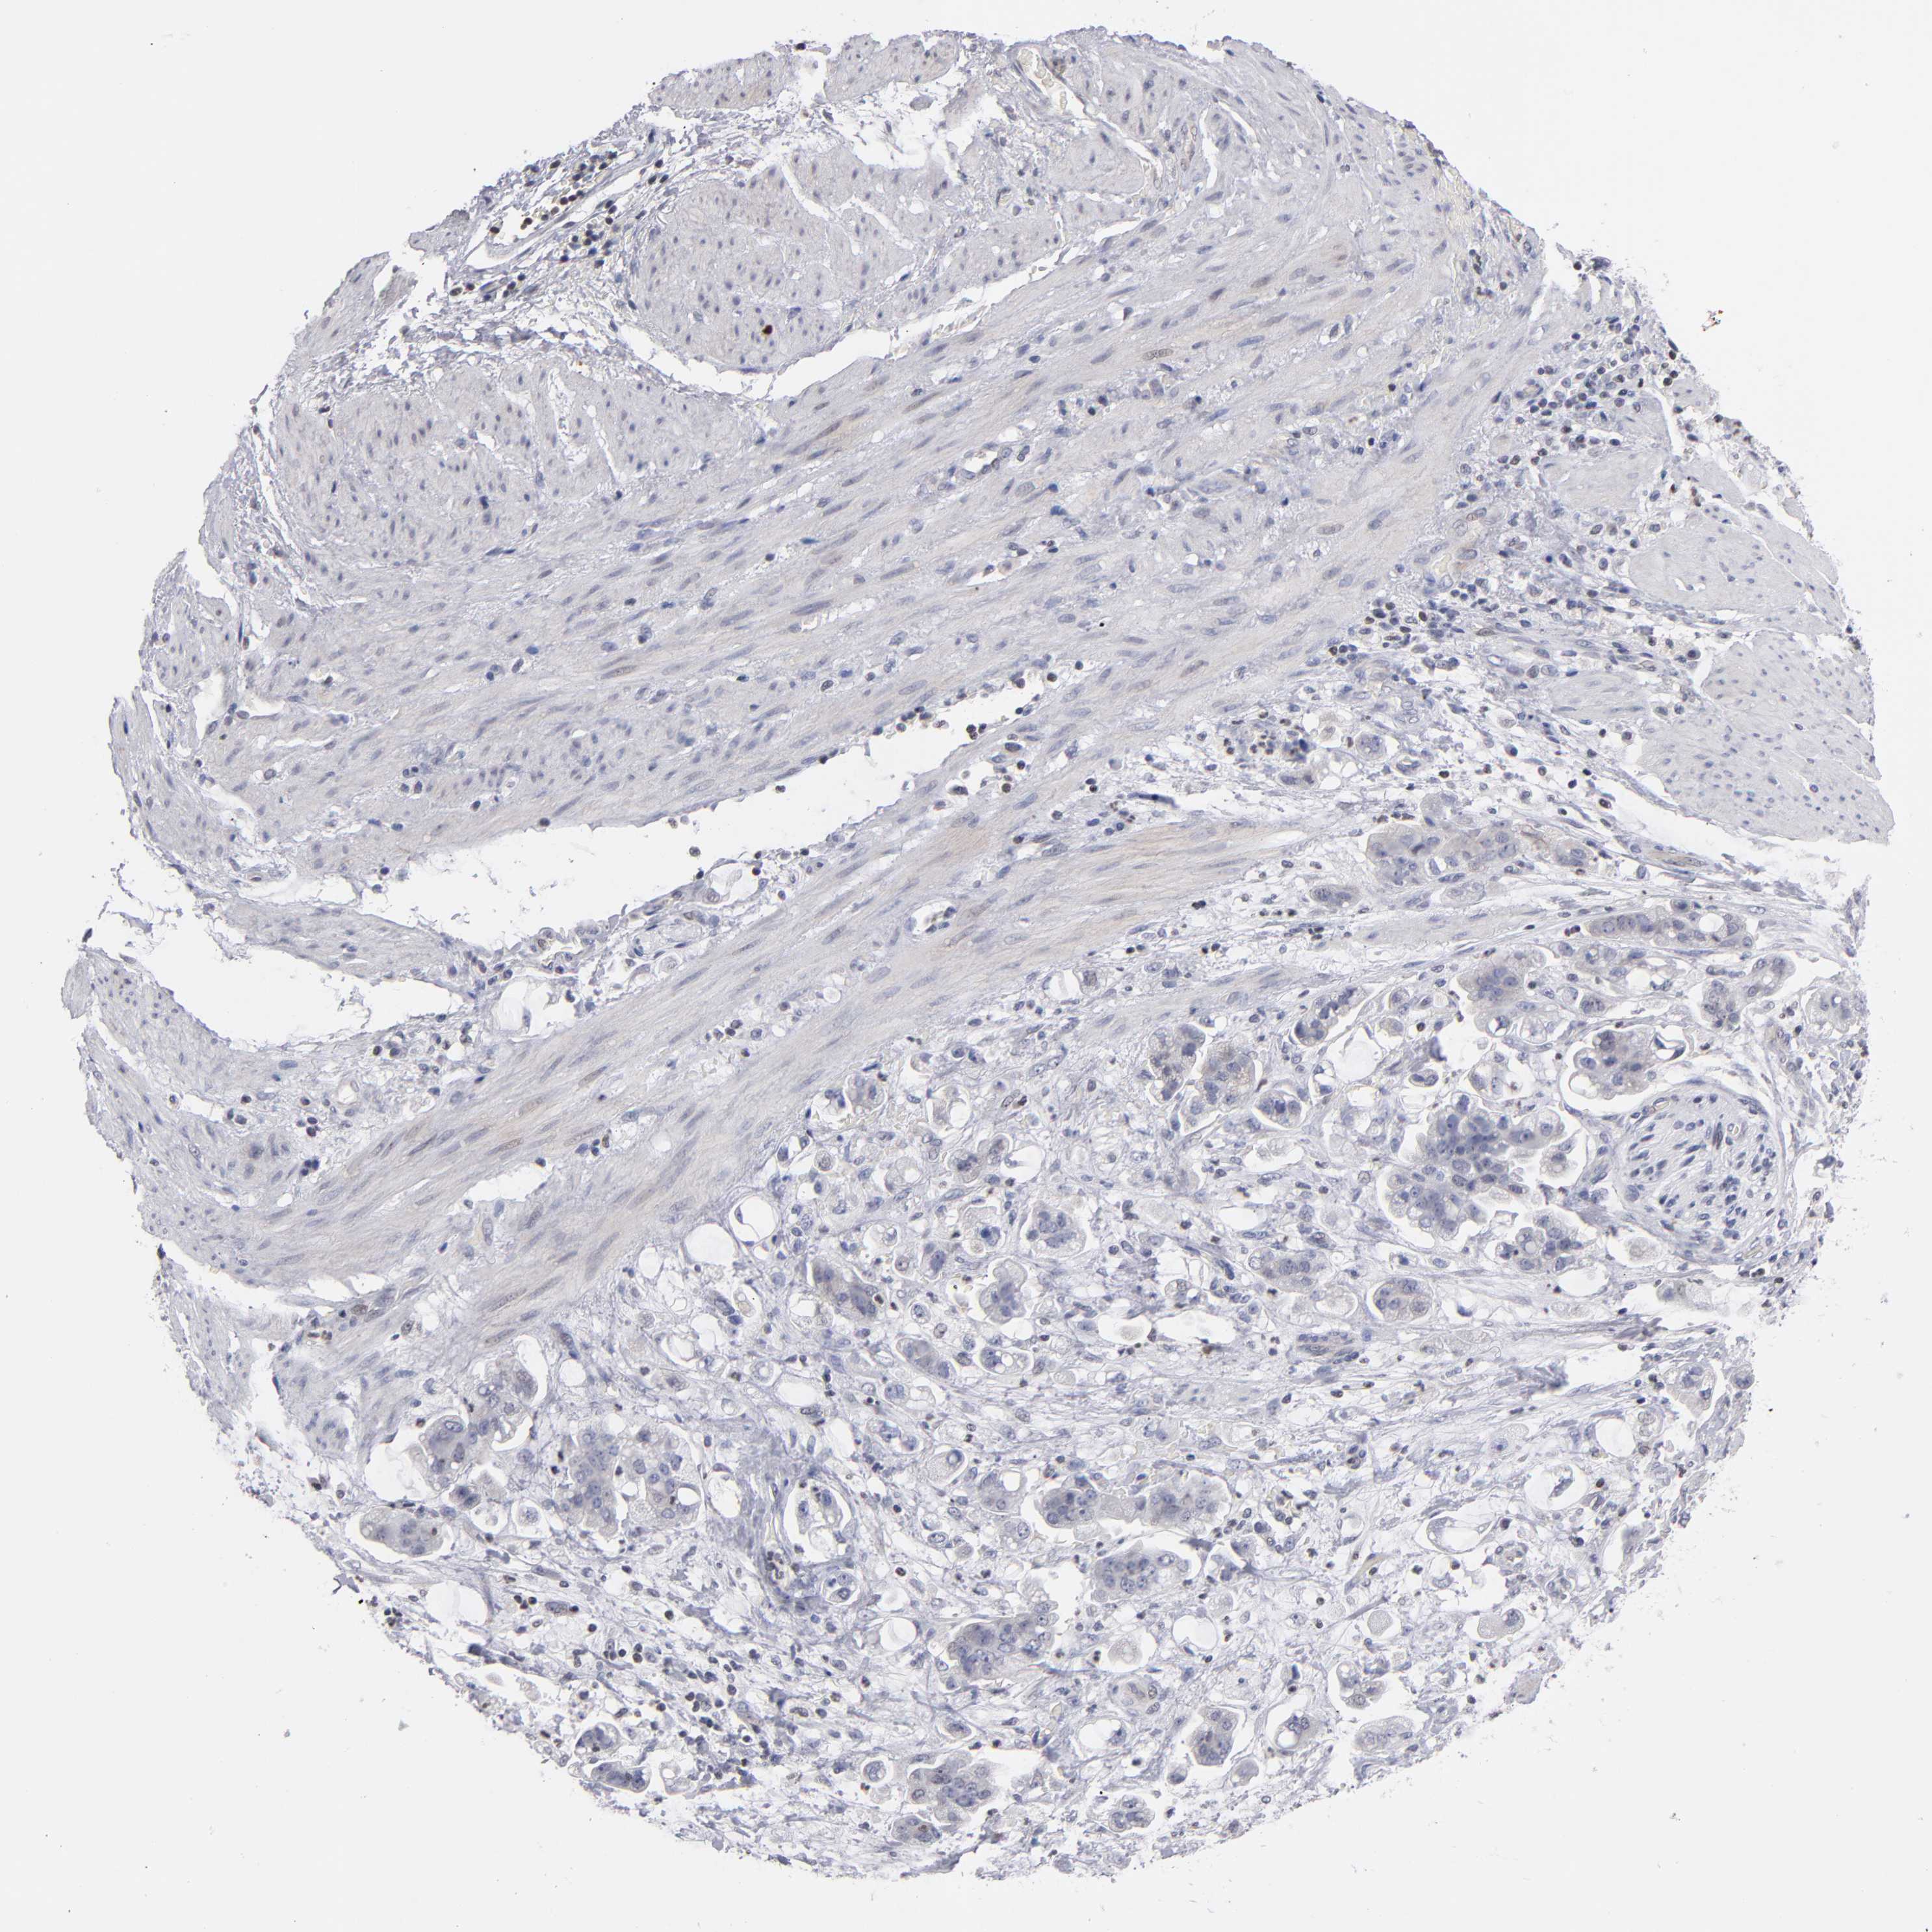

STOMACH CANCER - Protein expressioni

A mouse-over function shows sample information and annotation data. Click on an image to view it in a full screen mode. Samples can be filtered based on level of antibody staining by selecting one or several of the following categories: high, medium, low and not detected. The assay and annotation is described here.

Note that samples used for immunohistochemistry by the Human Protein Atlas do not correspond to samples in the TCGA dataset.

Antibody stainingi

Antibody staining in the annotated cell types in the current human tissue is reported as not detected, low, medium, or high, based on conventional immunohistochemistry profiling in selected tissues. This score is based on the combination of the staining intensity and fraction of stained cells.

Each image is clickable and will lead to virtual microscopy that enables deeper exploration of all samples and also displays staining intensity scores, fraction scores and subcellular localization as well as patient and tissue information for each sample.

Antibody HPA001874

Staining

High

Medium

Low

Not detected

Intensity

Strong

Moderate

Weak

Negative

Quantity

>75%

75%-25%

<25%

None

Location

Nuclear

Cytoplasmic/membranous

Cytoplasmic/membranous,nuclear

Adenocarcinoma, NOS

Adenocarcinoma, High grade